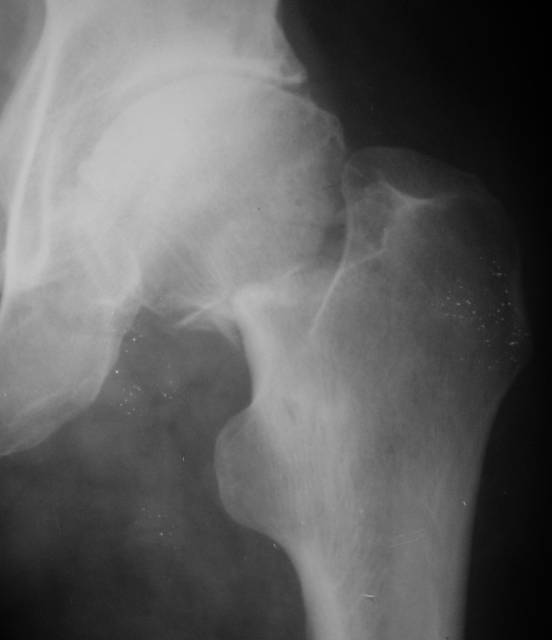

Еще пара фото, ситуация несколько иная, задачи те же, открытое вправление застарелого вывиха в 2002, молодой возраст. Сейчас госпитализирована для эндопротезирования.

Судя по снимку, максимум истинное укорочение около 4 см, что может быть коррегировано интраоперационно. Вопрос в другом: куда ставить ацетабулярный компонент в истинную или во вновь сформированную ( впадина диспластичная).

По рентгенограммам укорочение не более 4 см, остальное возможно за счет контрактуры. Опыта с низведением аппаратом Илизарова нет, но мы одномоментно такие укорочения корригировали вполне успешно (в год 5-10 именно таких и проходит). Лишние этапы пожалуй только будут способствовать инфекции. Доступ чаше применяем передне-наружный, а вот протез наверное поставили бы здесь на цементе - остеопороз выражен.

Ортопедическое укорочение пострадавшей ноги может быть и 7, и 10 см. за счет контрактур в тазобедренном суставе, а вот истинное укорочение, судя по представленным рентгенограммам, вряд ли больше 4 см.

В данном случае возможно выполнить одномоментное эндопротезирование тазобедренного сустава без предварительного низведения бедра. В ходе выполнения операции неизбежен релиз проксимального отдела бедра, что повлечет за собой значительную кровопотерю. Высокая травматичность данного вмешательства безусловно требует соответствующей подготовки и материально-технического обеспечения.